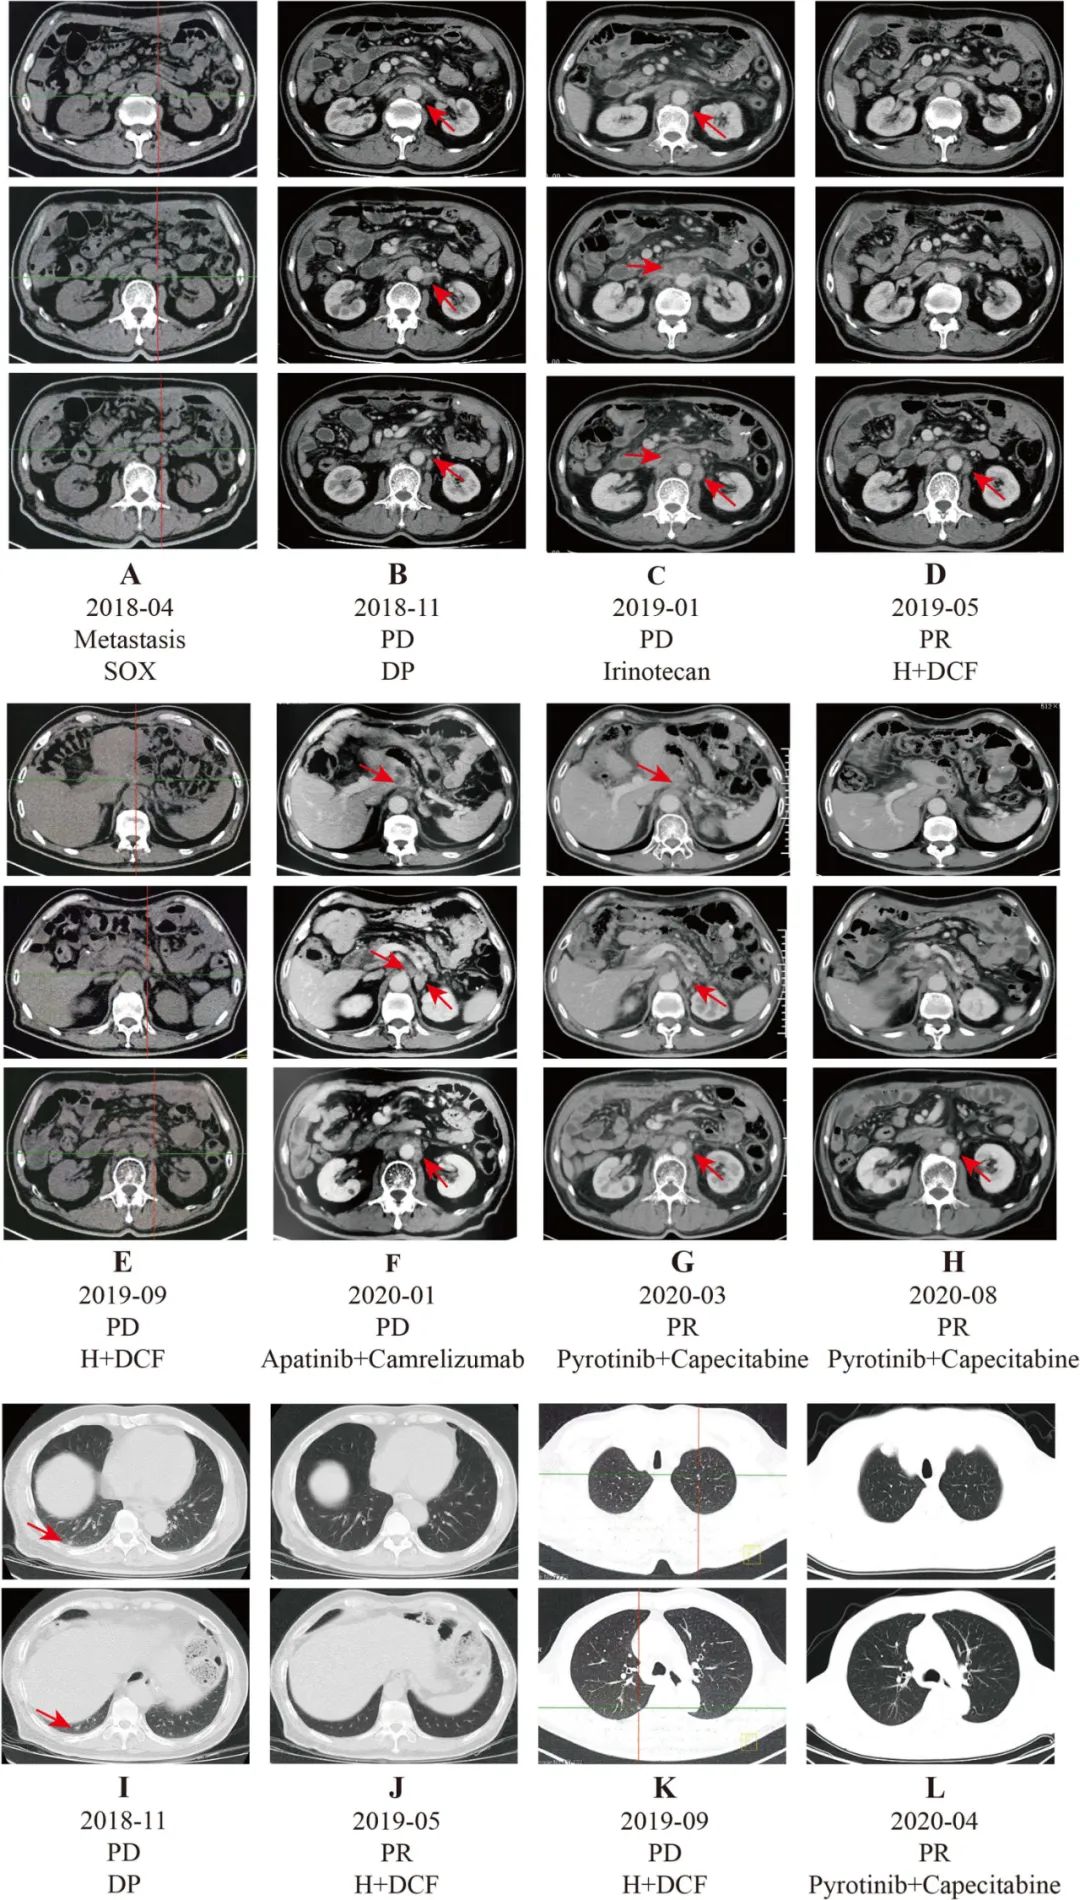

2019年后曲妥珠单抗纳入上海医保范畴,故建议患者曲妥珠单抗联合化疗。患者2019-01开始行曲妥珠单抗+DCF方案(多西他赛+顺铂+5-Fu)方案治疗。经2个周期治疗后,腹部CT显示腹膜后淋巴结部分缓解(PR)。4个周期治疗后,胸部CT示肺转移消失,腹部CT示腹膜后淋巴结PR。2019年9月PET-CT示左、右肺新结节,腹膜后多发肿大淋巴结。最大淋巴结长度约2.4 cm,最大SUV为10.75。CA199 (3988.0 U/mL)和CEA (30.2 ng/mL)显著升高。综合考虑,患者病情进展。

晚期胃癌患者经过第四线治疗后,已无标准的治疗。我们建议进行基因检测,患者拒绝。综合考虑,给予抗血管生成(阿帕替尼)联合抗PD-1抑制剂(卡瑞利珠单抗)治疗。经过两个周期的治疗后,腹部CT扫描显示病灶稳定。之后,我们又给病人进行了两个周期的治疗。2020年1月CT示腹膜后淋巴结略增大,CA199 (13725.0 U/mL)、CEA (48.3 ng/mL)明显升高。

患者病情进展后行基因检测。NGS测序结果示HER2基因拷贝数增加,HER2基因未发生突变。基于新型HER2靶向药物吡咯替尼与卡培他滨联合治疗可用于曲妥珠单抗耐药的乳腺癌患者。因此,患者于2020年1月行吡咯替尼联合卡培他滨治疗。三个周期后,腹部CT扫描显示腹膜淋巴结PR。四个周期后,胸部CT扫描显示肺结节消失。与此同时,CA199和CEA呈稳步下降趋势。2020年8月腹部CT示腹膜后淋巴结PR。患者对吡咯替尼治疗耐受良好,未观察到不良事件。PFS超过11个月。

图1. 患者治疗期间影像学评估资料变化情况